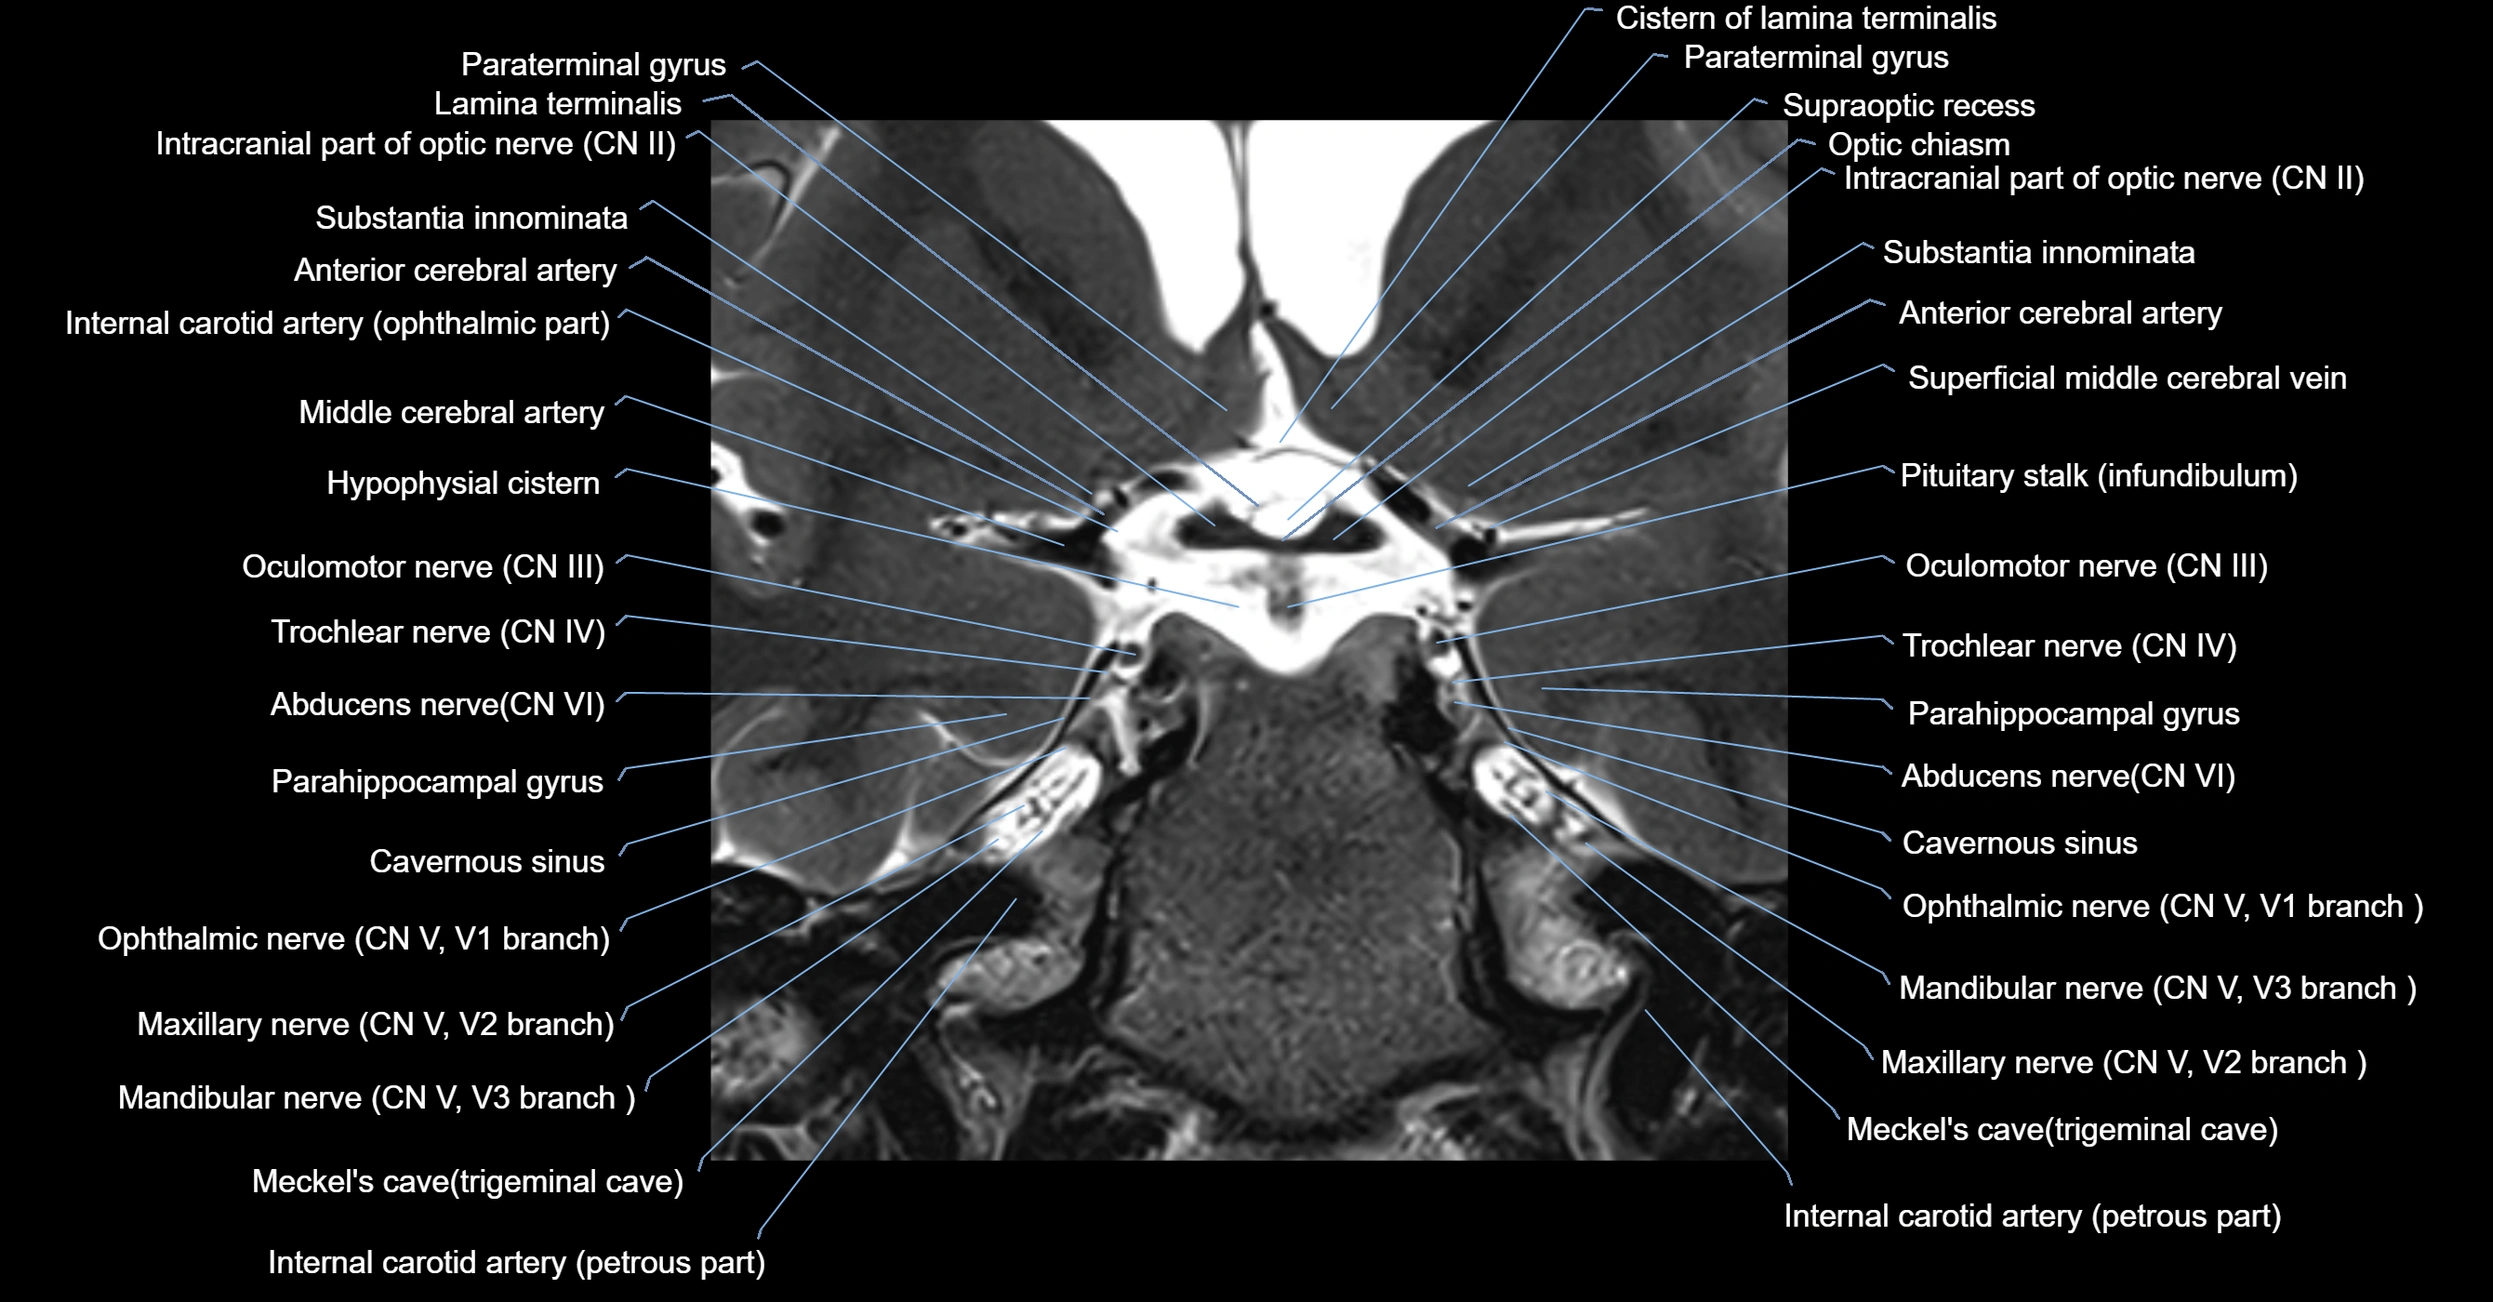

MRI Appearance

-

The abducens nerve is a small, thin, linear structure

Best visualized on high-resolution T2-weighted 3D MRI sequences (e.g., FIESTA or CISS)

Seen as a hypointense (dark) line running from the brainstem at the pontomedullary junction, traversing the prepontine cistern, and entering Dorello’s canal under the petrosphenoidal ligament, then into the cavernous sinus, and finally the orbit

May be challenging to visualize in standard MRI due to its small size

Pathology may be inferred by absence, displacement, or enhancement of the nerve

MRI images